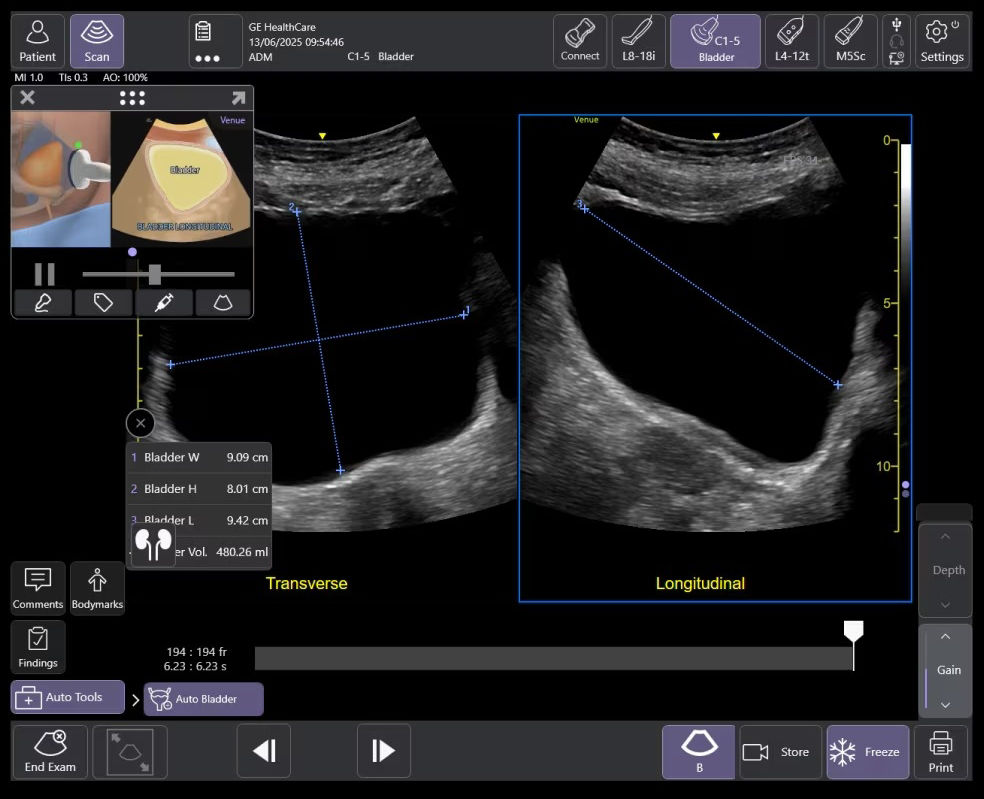

AI-enabled Auto Bladder Volume

Auto Bladder Volume provides rapid and easy urinary bladder volume measurements, saving clinicians valuable time and enhancing clinical accuracy. It measures bladder dimensions and calculates the bladder volume from two views: transverse and longitudinal.

ai-enabled-auto-bladder-volume-ci-new